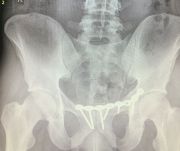

3. Pelvic fracture called also open book fracture in a 27-year-old male.

Treatment: Open reduction internal fixation of pubic symphysis and percutaneous fixation of the left sacroiliac joint

I. Before surgery II. Post-surgery, anteroposterior x-ray of pelvis showing one plate and six screws in pubic symphysis and one large screw in the left sacroiliac joint